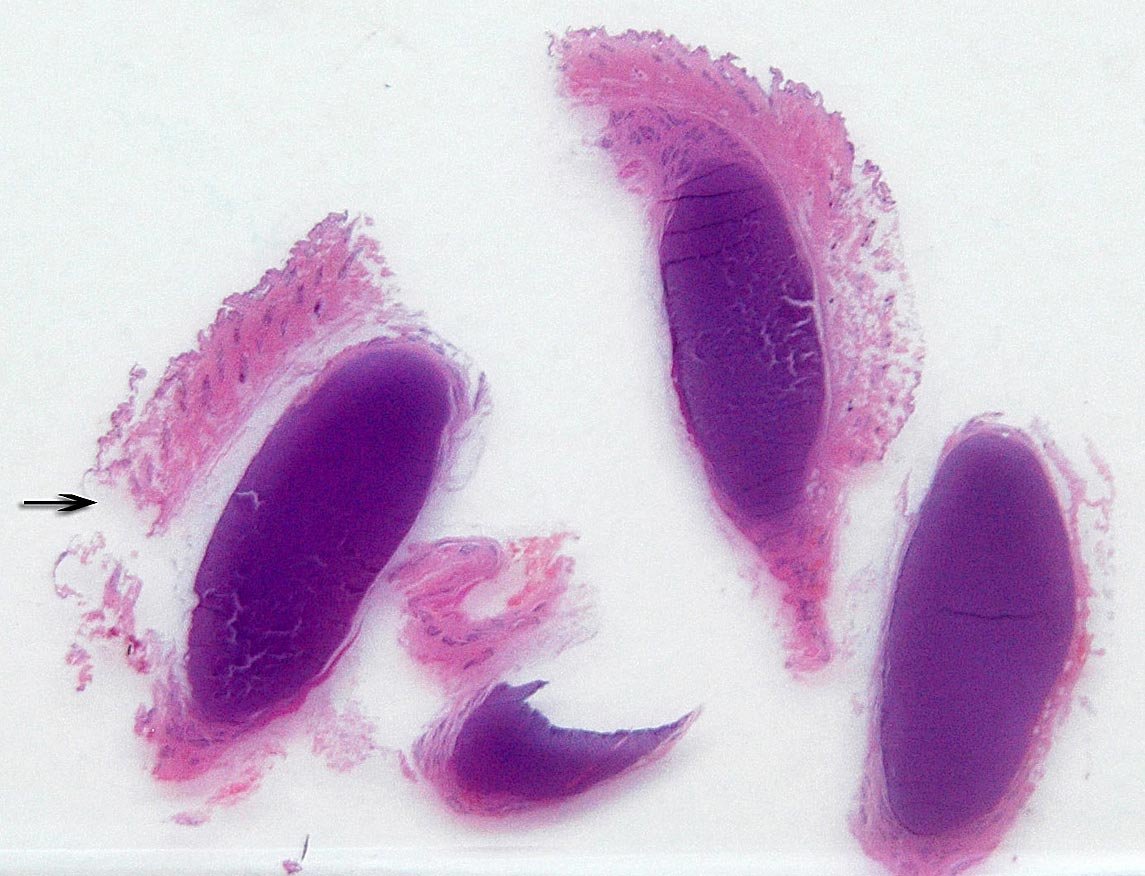

Hallazgos microscópicos:

Se recibe una masa de 8.0 x 5.50x 2.0cms de diámetro. Al seccionarla longitudinalmente, se observa un tejido blanco rodeado por otro tejido semejante a adiposo.

La masa estaba debajo de la dermis. Fig.1.

Fig.1. La flecha superior indica el borde inferior de la dermis. La otra flecha muestra la masa inmersa en el tejido adiposo. Mas profundamente se ve el tejido adiposo.